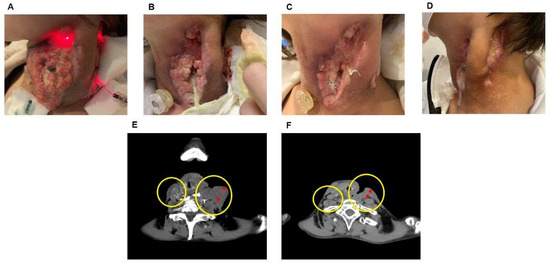

3.2. Case of the Effect of PDT on Hypopharyngeal Cancer